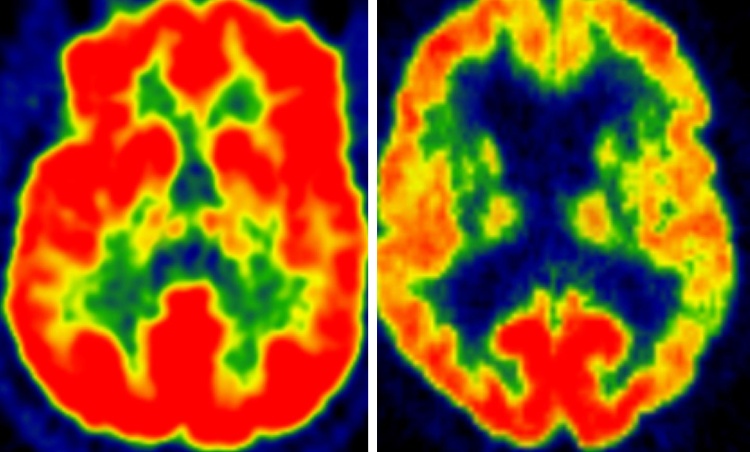

I dati sull'intensità dell'attività fisica sono stati quindi analizzati statisticamente per determinare quanto corrispondevano al metabolismo del glucosio - una misura della salute e dell'attività dei neuroni - nelle aree del cervello note per avere un metabolismo del glucosio depresso nelle persone affette da Alzheimer. Per misurare il metabolismo del glucosio del cervello, i ricercatori hanno usato una tecnica speciale di scansione chiamata tomografia a emissione di positroni con 18F-fluorodeossiglucosio (FDG-PET).

L'attività fisica moderata è stata associata a un metabolismo più sano del glucosio (livelli più elevati) in tutte le aree analizzate del cervello. I ricercatori hanno notato un beneficio graduale: i soggetti che hanno trascorso almeno 68 minuti al giorno impegnati in attività fisica moderata hanno mostrato profili migliori del metabolismo del glucosio rispetto a quelli che hanno trascorso meno tempo.